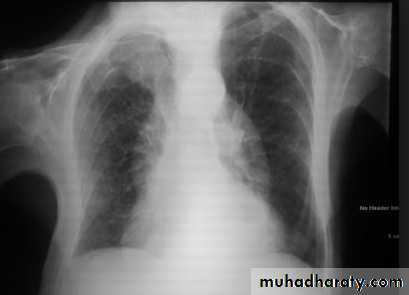

8- assess technical quality of the film: correctly exposed routine PA CXR is one in which the ribs and spine behind the heart can be identified but lung not overexposed.straight film is one where the medial ends of clavicles are equidistant from thoracic verteb.